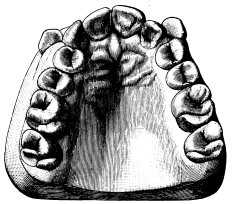

Fig. 21.

|

(a) Normal upper first permanent molar. (b) Oblique rooted upper first permanent molar. (c) Normal upper second permanent molar. (d) Oblique rooted second permanent molar. |

There is an abnormality of the upper molars which may with advantage be mentioned here. In this deformity the posterior buccal root is situated in a plane much internal to the anterior—in other words, it is an exaggeration of the normal arrangement. Such teeth have been termed by Mr. Booth Pearsall “oblique rooted” (fig. 21). The abnormality is met with most frequently in the third molar, sometimes in the second, rarely in the first. The difficulty encountered in extracting these teeth is{27} that the outer blade of the forceps tends to slip round. Oblique-rooted teeth can at times be diagnosed by noting an undue prominence of the alveolus over the anterior buccal root, and are best removed with forceps similar to that shown in fig. 20.